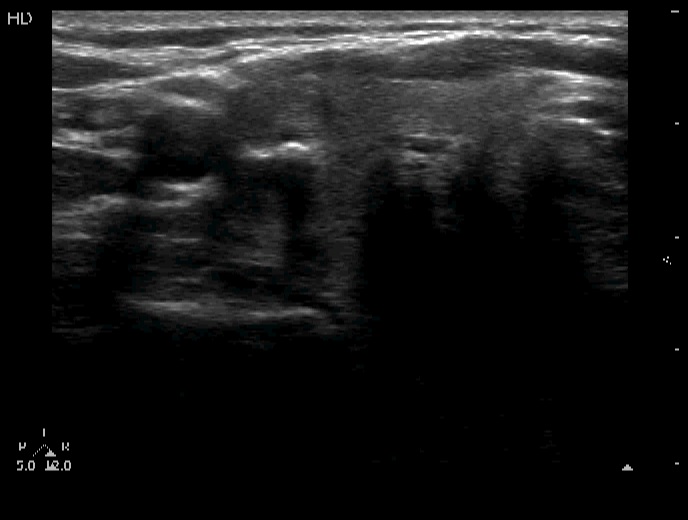

Right lobe, horizontal view

Right lobe, transverse view. There is a coarsely calcified lesion in the lateral part of the lobe.